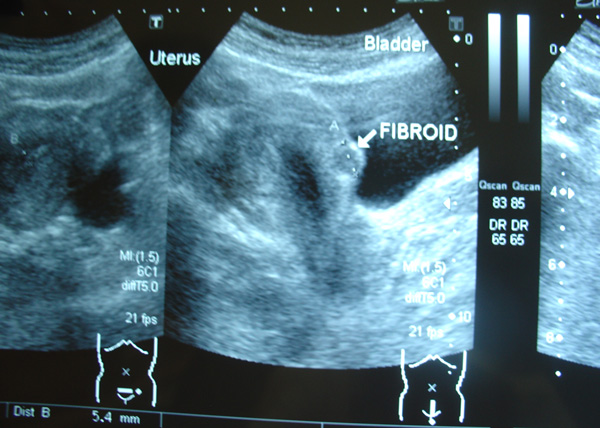

Jane (not real name, H-237) was 43 years old when she was diagnosed with breast cancer in 2009. Earlier Jane had undergone surgery to remove a small ovarian cyst. Unfortunately an ultrasound in August 2010 showed:

- The uterus contains a 1.2 cm fibroid in the anterior wall.

- A 3 cm thin walled cyst in the left ovary which appears benign.